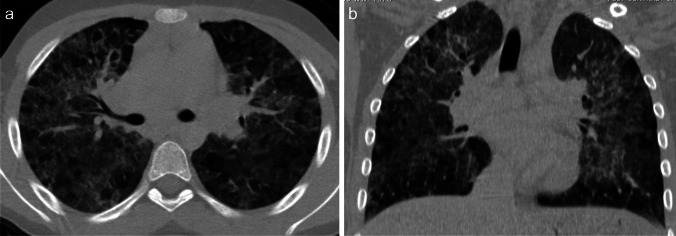

Radiological findings of hypersensitivity pneumonitis vary according to the stage of the disease. Although chest radiography can help identify the disease, CT is increasingly used, as it is more sensitive for subtle ground-glass opacities and identification of fibrosis [69]. In the acute/inflammatory form, CT typically shows patchy or diffuse bilateral ground-glass opacities, small centrilobular nodules, lobular areas of reduced attenuation and vascularization (i.e., mosaic attenuation), and air trapping on expiratory images (Fig. 9). Thickening of the interlobular septa, traction bronchiectasis, and a subpleural honeycomb pattern are signs of chronic/fibrotic form. The lung bases are typically spared [70].

Fig. 9.

Axial (a) and coronal (b) contrast-enhanced lung window computed tomography images in a 9-year-old girl with a 3-month history of chronic dry cough, wheezing, and loss of weight demonstrate patchy bilateral ground-glass opacities, small centrilobular nodules, lobular areas of reduced attenuation and vascularization (i.e., mosaic attenuation), and interlobular septal thickening with sparing of the lung bases. No associated features of chronic lung disease. Lung biopsy confirmed hypersensitivity pneumonitis. On further investigation, her mother also had similar clinical symptoms. The family had started breeding pigeons 6 months prior. When the antigen was removed, the child’s symptoms completely resolved, and follow-up chest radiography performed 3 months later (not shown) was normal